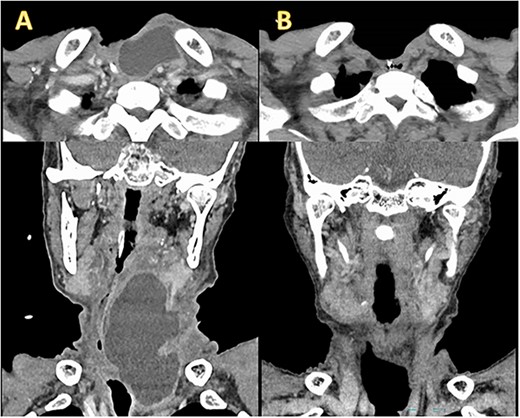

A 77-year-old man underwent a total laryngectomy with modified bilateral ND for advanced laryngeal squamous cell carcinoma (cT4aN0M0, stage IVA). A small chylous leakage was observed on postoperative day (POD) 1. As the chylous leakage did not improve with fasting, wound compression, and drainage, ligation of the thoracic duct and its branches was attempted under general anesthesia on POD3. However, the leakage persisted, and computed tomography (CT) on POD17 revealed a lymphatic cyst extending from the peritonsillar space to the upper mediastinum (Fig. 1A). Therefore, we decided to administer OK432 sclerotherapy. After draining the leaked chyle, we injected 2KE of OK432 diluted with 4 mL of normal saline and compressed the wound. The day after the injection, the chylous leakage completely stopped without complications. Seven days after the first injection, a second dose of OK432 was administered in a similar manner. CT on POD 83 confirmed the complete disappearance of the retained lymph (Fig. 1B).

Enhanced CT before and after OK432 injection. (A) Before OK432 injection. Cervical CT shows a chylous leakage in the left supraclavicular fossa. (B) After two cycles of OK4432 injection. The chylous leakage completely disappeared after OK432 sclerotherapy.